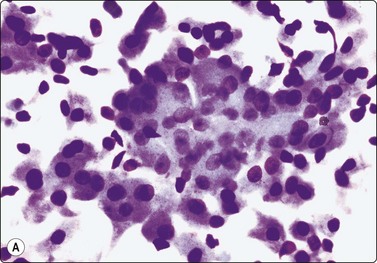

Nasopharyngeal carcinoma (NPC) (Figs 4.8, 4.9, and 5.59)44-47

image

Fig. 4.8 Nasopharyngeal carcinoma (squamous cell carcinoma, WHO type II)

Epithelial fragment of spindly and basaloid squamous epithelial cells with no evidence of keratinization (Pap, HP).

image image

Fig. 4.9 Nasopharyngeal carcinoma (undifferentiated, lymphoepithelial type, WHO type III)

Loose clusters of undifferentiated epithelial cells with vesicular nuclei, prominent nucleoli and pale fragile cytoplasm. Background of lymphocytes. (A, MGG, HP; B, H&E, HP).

Criteria for diagnosis (undifferentiated carcinoma nasopharyngeal type (UCNT)/WHO type III/lymphoepithelial carcinoma)

Undifferentiated malignant cells, single and in clusters,

Variable amount of pale, fragile cytoplasm,

Large vesicular nuclei with prominent central nucleoli,

Admixture with, and background of, lymphoid cells, often with prominent plasma cells,

Ancillary tests: neoplastic cells positive for cytokeratin, negative for lymphocyte markers. EBV-associated nuclear antigen.

Nasopharyngeal carcinoma (NPC) is a clinicopathologic entity different from other squamous cell carcinomata of the head and neck. It is distinguished by its particular histology, geographic distribution, relationship to Epstein-Barr virus, and the absence of an alcohol or tobacco etiological relationship. A proportion of NPCs show squamous differentiation and the cytological pattern of non-keratinizing squamous cell carcinoma (squamous cell carcinoma/WHO type II) (Fig. 4.8). Keratinized cells (WHO type I) are uncommonly found. The majority of NPC are poorly differentiated or undifferentiated. Cells from undifferentiated NPC (UCNT, WHO type III) form loose clusters with no specific microarchitectural pattern, and are usually mixed with lymphoid cells. In the ‘lymphoepitheliomatous’ type (Schmincke-Regaud) the cells tend to be less cohesive, resembling Hodgkin’s disease or large cell non-Hodgkin lymphoma. However, in NPC, the malignant cells are still clustered and have more abundant pale cytoplasm contrasting with the lymphoid cells in the background (Fig. 4.9). Plasma cells are frequently found among the lymphoid cells. Immunostaining for cytokeratin and a pan-lymphocyte marker is helpful. Epstein-Barr virus-associated nuclear antigen is demonstrable by anticomplement immunofluorescence in undifferentiated tumors. Other patterns of growth may occur and may cause diagnostic problems; for example, spindle cell forms may be difficult to recognize as carcinoma.

NPC frequently presents to the cytologist as a lymph node metastasis in the neck without a known primary. Cytological recognition is important since the primary is often clinically occult.